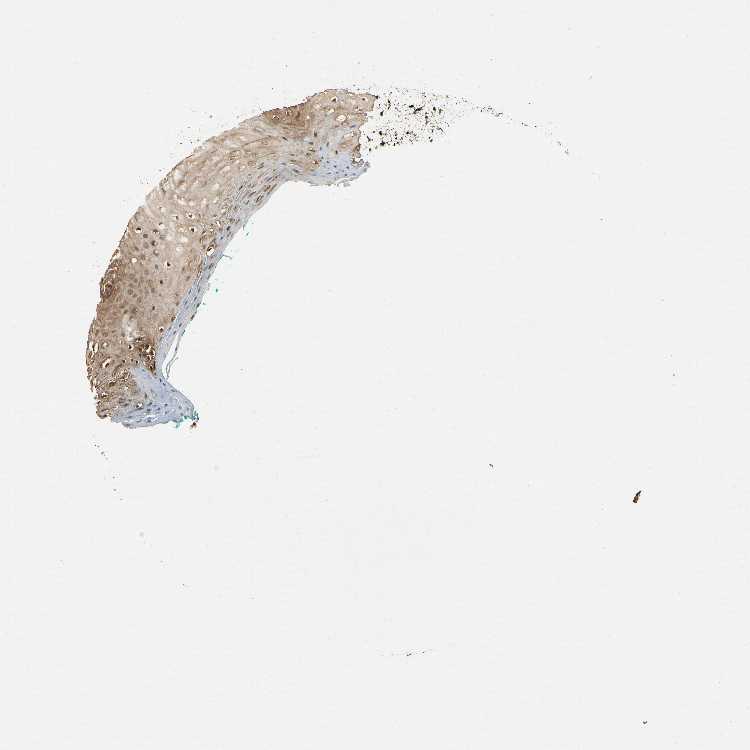

TISSUE PRIMARY DATA ORAL MUCOSA Show tissue menu

ORAL MUCOSA - Antibody stainingi

Antibody staining in the annotated cell types in the current human tissue is reported as not detected, low, medium, or high, based on conventional immunohistochemistry profiling in selected tissues. This score is based on the combination of the staining intensity and fraction of stained cells.

Each image is clickable and will lead to virtual microscopy that enables deeper exploration of all samples and also displays staining intensity scores, fraction scores and subcellular localization as well as patient and tissue information for each sample.

Antibody HPA007925Antibody CAB010286

Squamous epithelial cells MediumLow